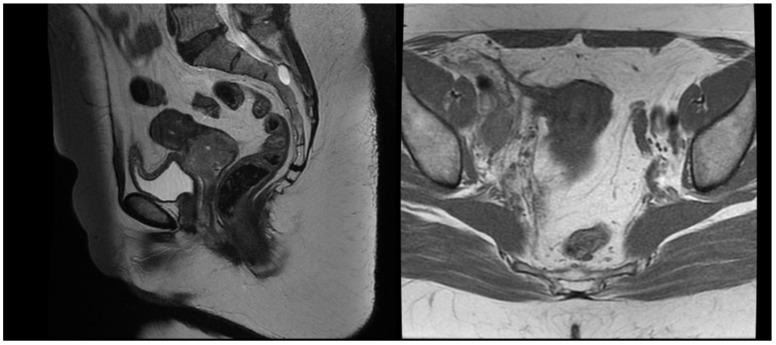

: The purpose of this report is to investigate the feasibility of combined modality treatment in a case of locally advanced cervical cancer in a patient with inherited epidermolysis bullosa as well as to suggest a protocol for cervical electronic brachytherapy. : The patient was treated with image-guided external beam radiotherapy and concomitant chemotherapy to a dose of 45 Gy in 25 fractions with a simultaneously integrated boost of 55 Gy in involved lymph nodes. The maximal skin dose was 34.09 Gy. Intracavitary electronic brachytherapy was applied to the uterine cervix in 4 fractions of 7 Gy and contributed no dose to the skin. : The treatment was tolerated well with no early toxicity. During the 3-month period of follow-up, no adverse events of grade 2 or higher were detected, and no exacerbation of skin lesions was noted. : This is the first report of treatment of cervical cancer in a patient with inherited epidermolysis bullosa where combined concurrent chemoradiotherapy and intracavitary electronic brachytherapy demonstrated feasibility and safety. The followed institutional protocol for treatment planning and delivery ensured low doses to organs and risk and reproducibility.

本报告的目的是探讨在一名患有遗传性大疱性表皮松解症的局部晚期宫颈癌患者中进行综合治疗的可行性,并提出一种宫颈电子近距离放疗方案。该患者接受了图像引导的外照射放疗和同步化疗,剂量为45 Gy,分25次进行,同时对受累淋巴结进行55 Gy的同步整合加量照射。最大皮肤剂量为34.09 Gy。对子宫颈进行了4次腔内电子近距离放疗,每次7 Gy,未对皮肤造成剂量。治疗耐受性良好,无早期毒性。在3个月的随访期间,未检测到2级或更高等级的不良事件,也未发现皮肤病变加重。这是首例关于遗传性大疱性表皮松解症患者宫颈癌治疗的报告,其中同步放化疗和腔内电子近距离放疗显示出可行性和安全性。后续的机构治疗计划和实施方案确保了对器官的低剂量、低风险和可重复性。